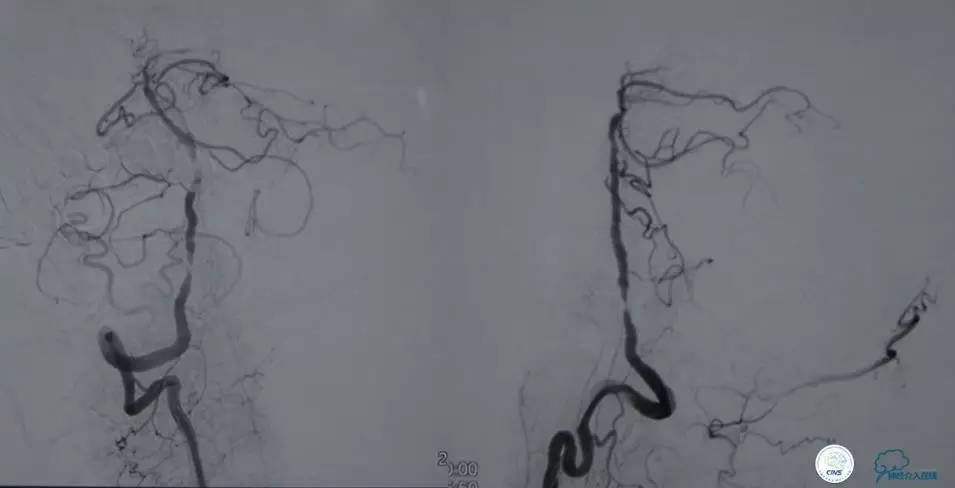

▼2014-12-08

▼Apollo 3.0*13mm

▼R-VA

▼第三天MRA